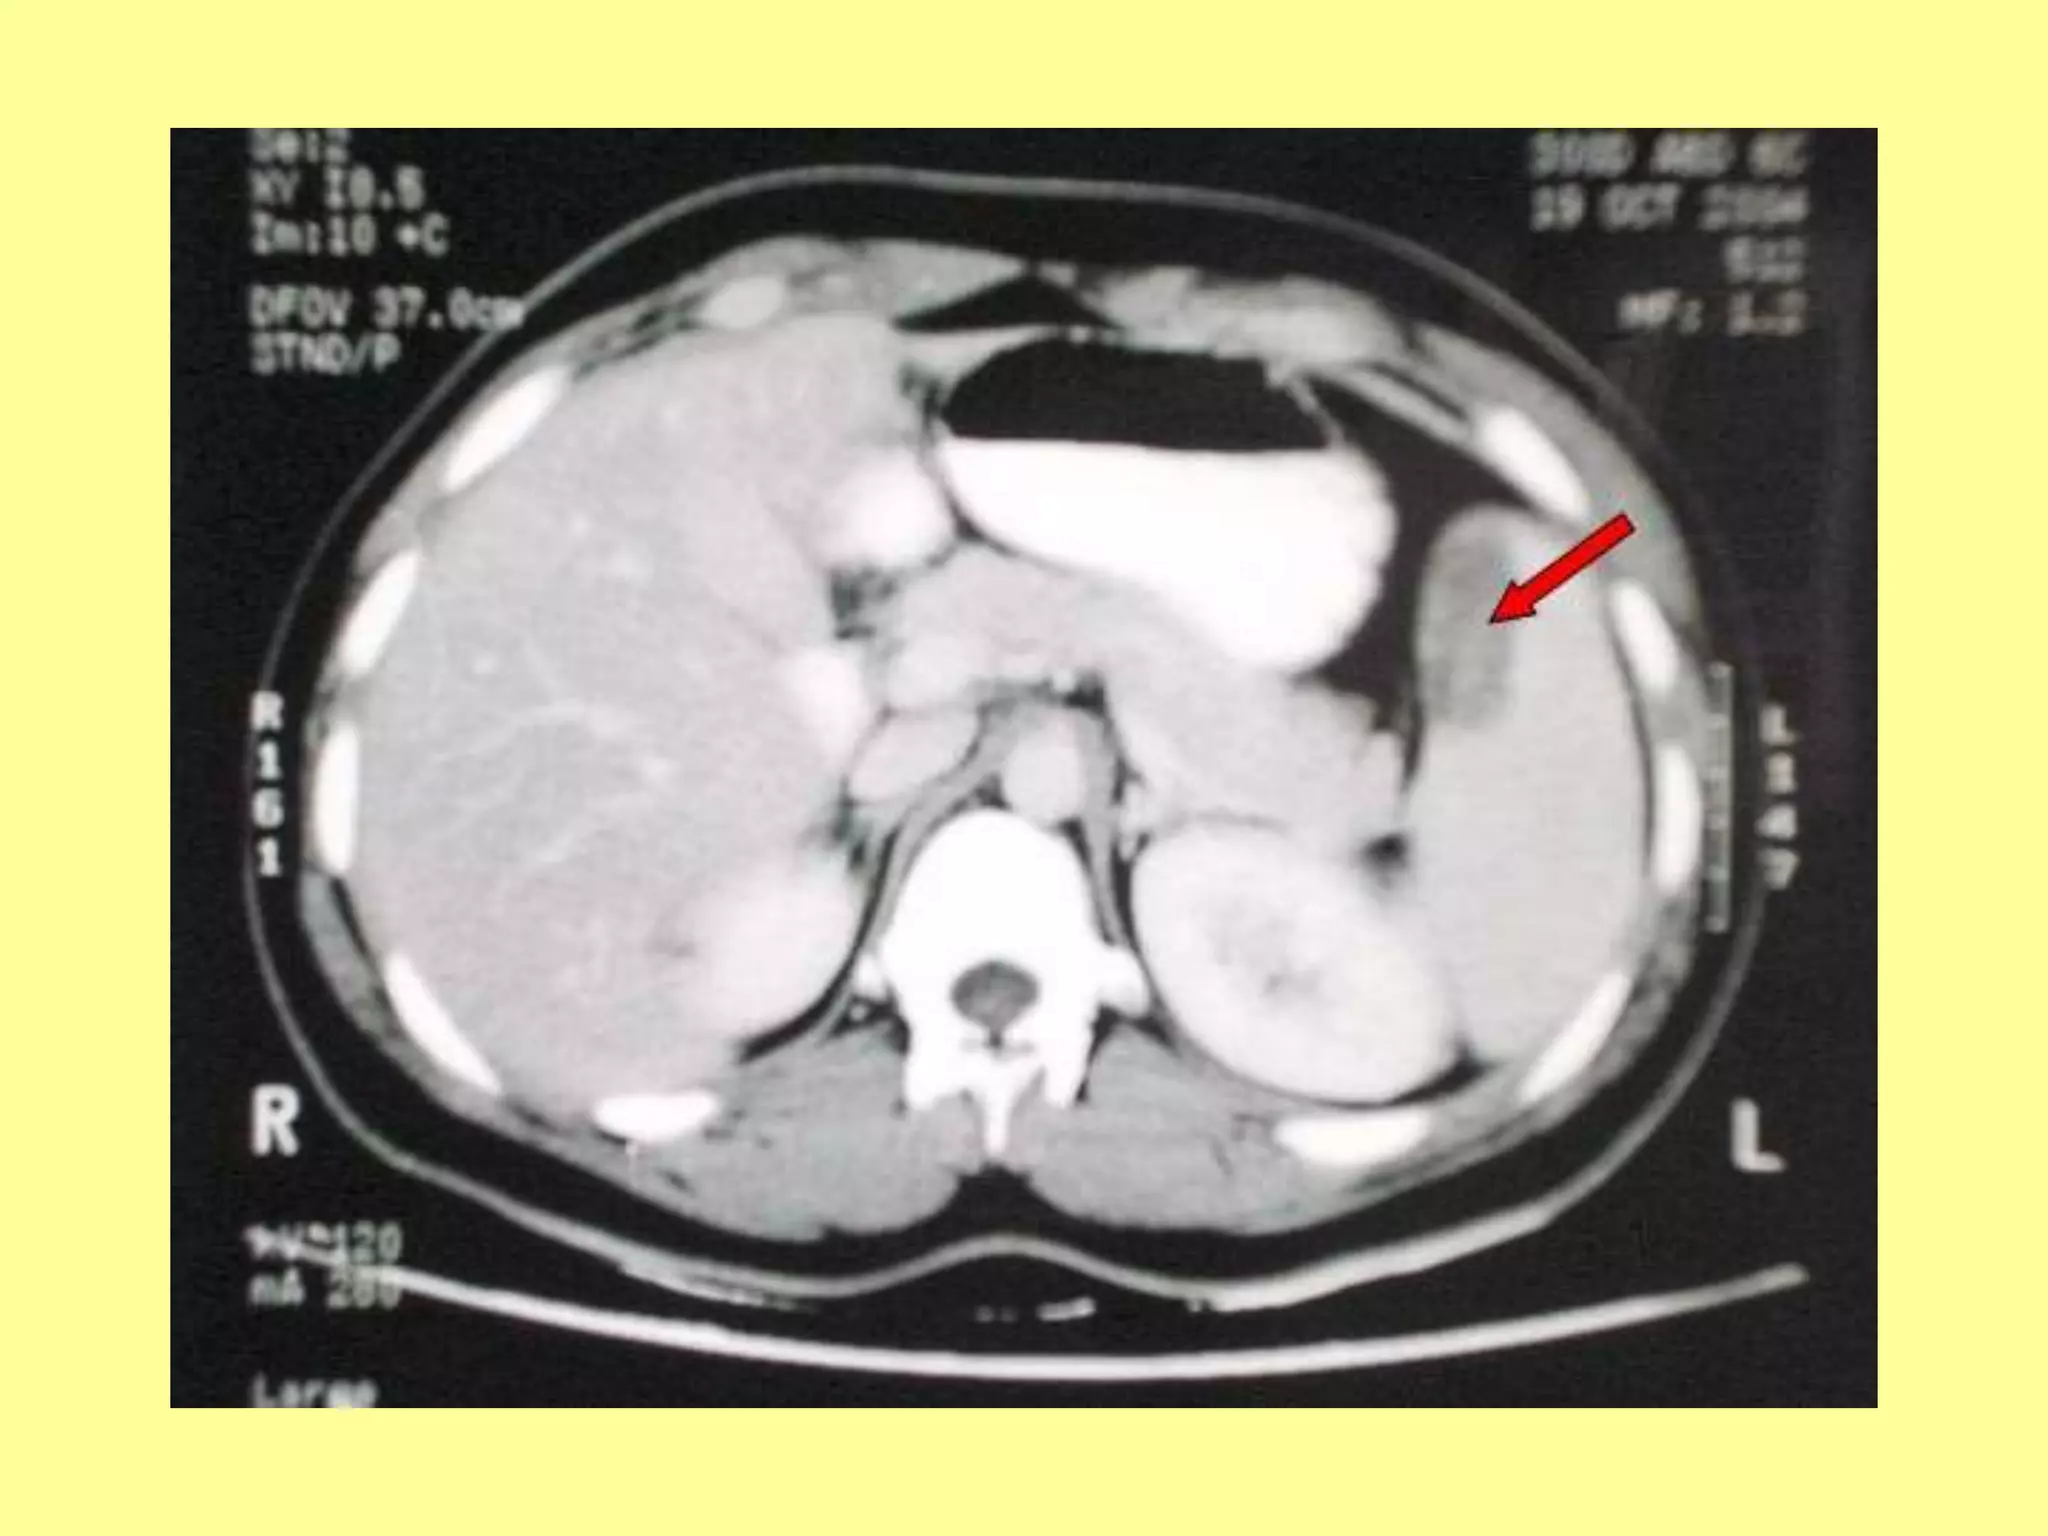

(b) CT.Scan abdomen

used for diagnosing

intraperitoneal injuries in

stable patients after blunt

trauma.

 Non operative approach:

The hepatic injury diagnosed

by CT in stable patient is now

non operative approach

practiced in many centers.

CT. Criteria for nonoperative

management include the

following: